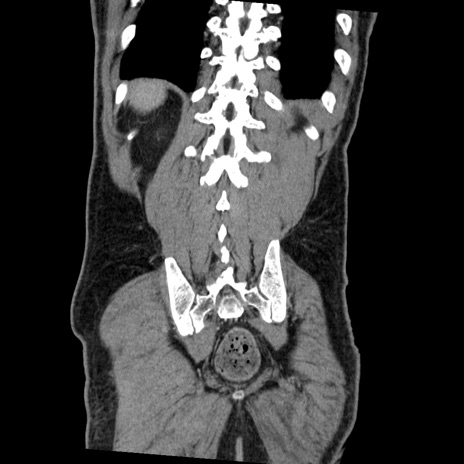

症例22(冠状断像)

【症例】50歳代男性

【主訴】腹痛

【現病歴】AVMからの被殻出血のため回復期リハ病棟入院中。 本日午後3時頃急に下腹部痛が出現した。

【既往歴】AVM、被殻出血、虫垂炎、高血圧

【身体所見】意識晴明、左半身不全麻痺、会話の理解は良好、36.5°C、腹部:膨隆、全体に板状硬、下腹部正中に圧痛点あり、反跳痛-、筋性防御不明、右下腹部にope scar

【データ】WBC 9400、CRP 0.06